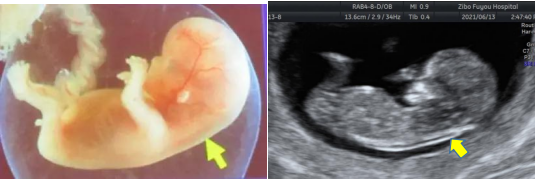

NT(nuchal translucency),即颈项透明层,指胎儿颈后部皮下组织内液体集聚的厚度,超声表现为胎儿正中矢状切面颈项后的带状无回声。

正常情况下,胚胎淋巴系统健全之前,少部分淋巴液聚集在颈部淋巴囊或淋巴管内,形成颈项透明层,一般在14周后会消退。如果由于遗传、解剖结构异常、感染等因素导致颈部淋巴管与颈静脉窦相通延迟,使颈部淋巴回流受到障碍,淋巴液过多的积聚在颈部,即表现为NT的增厚。